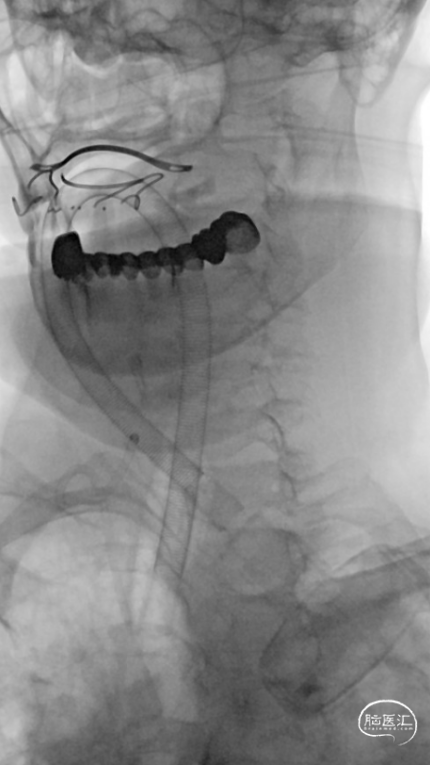

造影见RICA再通,RMCA M1段近端重度狭窄,约90%。

观察10分钟后,狭窄较前加重,局部不规则充盈缺损。术中即刻DynaCT未见造影剂染色。

将Synchro(0.014×300cm)微导丝外衬Gateway(2.0×15mm)球囊缓慢通过RMCA M1段狭窄处,球囊定位于RMCA狭窄处缓慢扩张,压力6atm。采用交换技术置入灌注微导管,并将4.0×16mm支架定位于狭窄处释放。